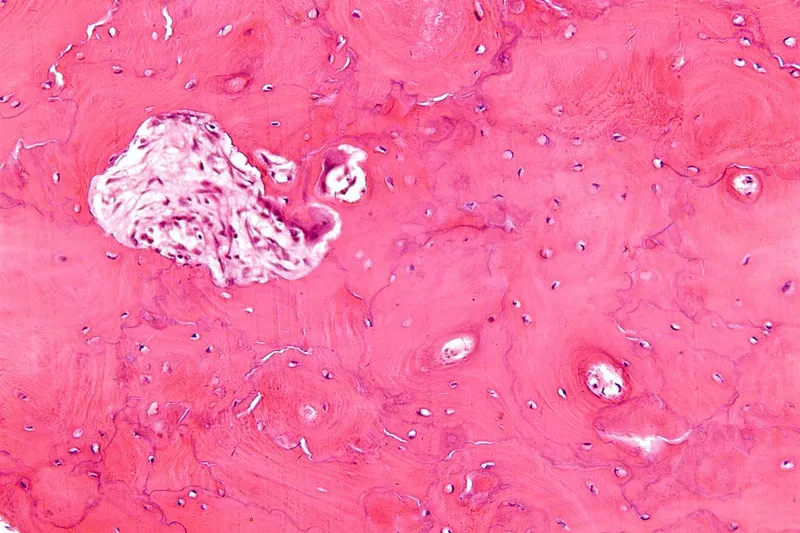

⭐ Histology: Pathognomonic "mosaic pattern" (jigsaw/cement lines) from irregular turnover.

- Biopsy: For suspected sarcoma; reveals mosaic pattern.